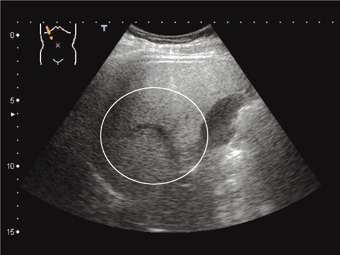

症例7:診断と解説。